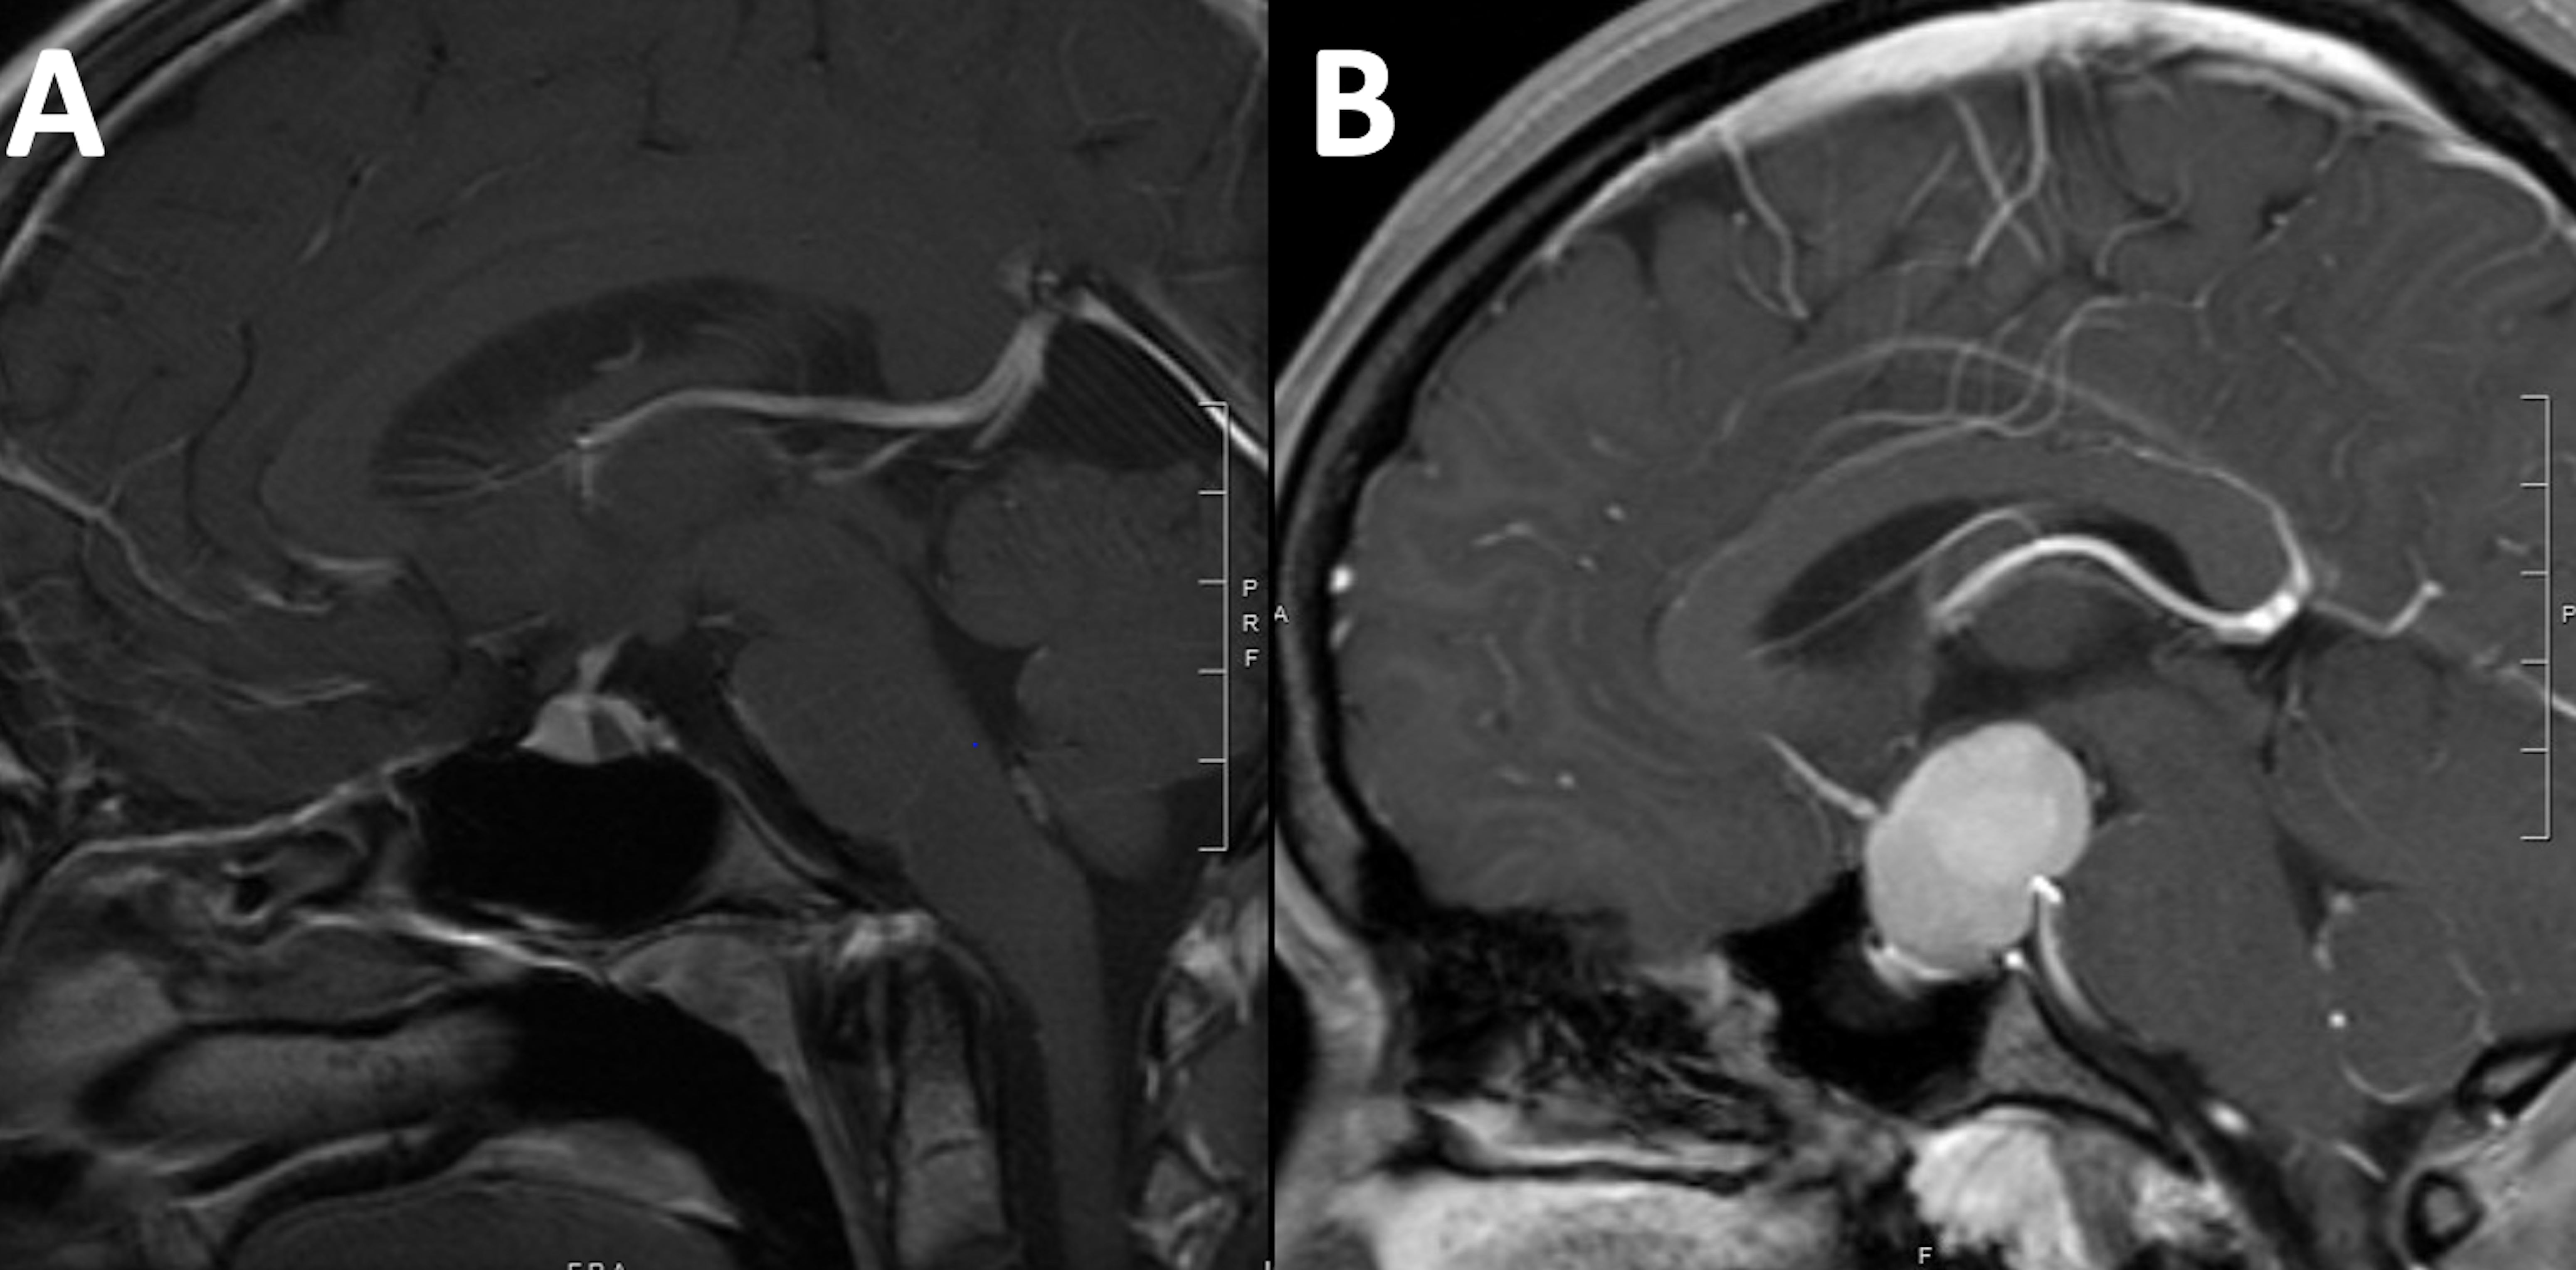

RCCs account for less than 1% of all intracranial masses [1,4-10]. Nevertheless, with the advent of modern diagnostic imaging modalities, RCCs are increasingly encountered as incidental findings during evaluation for unrelated clinical presentations [11]. RCCs are commonly small asymptomatic lesion; however, they often attain large size and exert mass effect on surrounding vital neurovascular structures, and hence become symptomatic. The most common clinical presentations include headache [6,12], vision loss, and endocrine dysfunction [4,6,10,13]. The diagnosis of RCCs is often challenging as they may resemble other cystic sellar lesions, including cystic pituitary adenomas, craniopharyngiomas, and arachnoid cysts (Figure 1).

Figure 1: Brain MRI T1WI sagittal view with intravenous Gadolinium contrast demonstrating different configurations of RCC. The typical configuration (A) is an ovoid intrasellar cyst that is located in the area of the intermediate lobe within the pituitary gland. Larger cysts (b) may attain different shapes and may resemble other lesions such as pituitary adenoma.